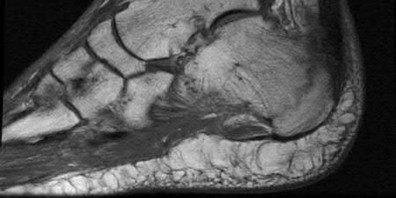

Question 8:

A 40-year-old male sustains a high-energy Pilon fracture. Initial treatment consists of a spanning external fixator across the ankle joint. Which of the following clinical findings best indicates that the soft tissue envelope has recovered sufficiently to permit definitive open reduction and internal fixation (ORIF)?

Correct Answer: Return of the 'wrinkle sign' on the anterior ankle skin

Explanation:

In the staged management of high-energy Pilon fractures, definitive ORIF must be delayed until the soft tissue envelope has adequately healed to minimize the risk of wound complications and infection. The return of skin wrinkles (the 'wrinkle sign') indicates a significant reduction in interstitial edema and is the widely accepted clinical milestone for proceeding with definitive fixation, typically 10 to 21 days post-injury.